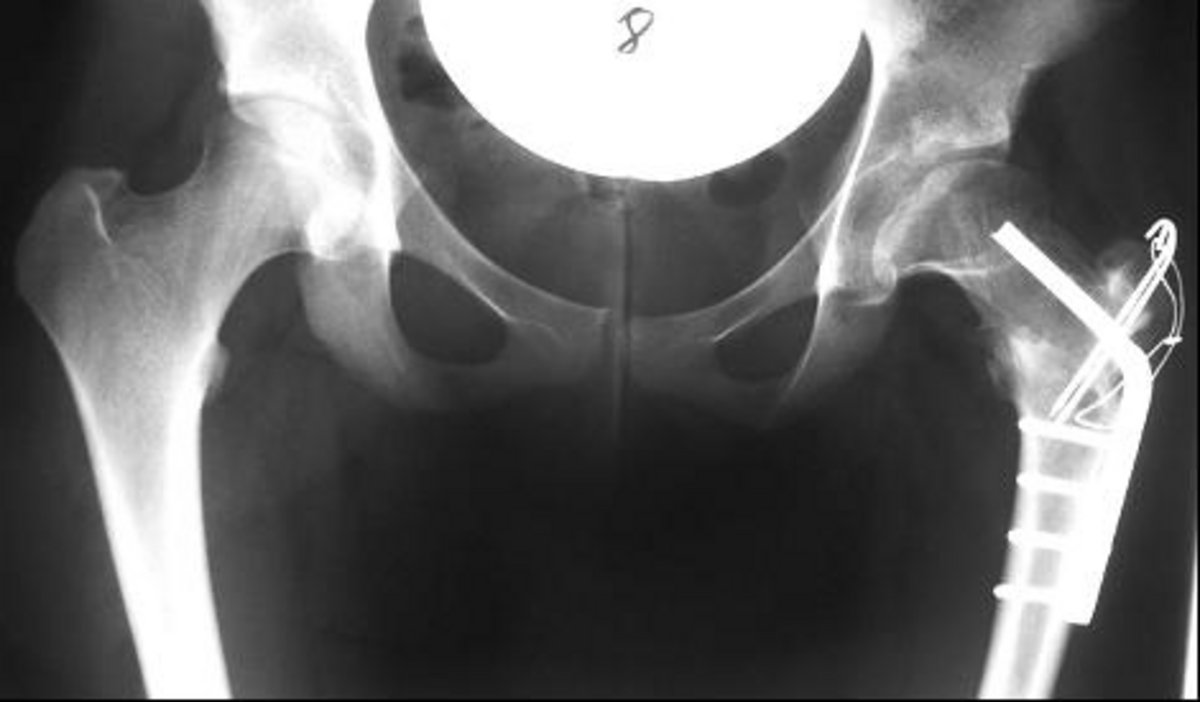

Hüftchirurgie

Die Entwicklung von neuen Hüftprothesenmodellen und neuen Operationstechniken hat die Hüftchirurgie in den letzten Jahren schnell vorangetrieben. Neue Operationstechniken wie die Hüftarthroskopie, die chrirugische Hüftluxation und Beckenschwenkoperationen stellen neue therapeutische Optionen dar.

Durch die neuen Therapieverfahren kann die Notwendigkeit eines künstlichen Hüftgelenkes oft hinausgezögert oder gar vermieden werden. Für Hüftarthrosepatienten stellt im Anfangsstadium die Hüftarthroskopie eine gute therapeutische Option dar. Zerstörte Knorpelanteile und Gelenklippenanteile (Labrum) können entfernt werden. Freie Gelenkkörper können ebenso mittels Arthroskopie geborgen werden.

Bei noch gut erhaltenem Hüftspalt und einzelnen knöchernen Wucherungen (Osteophyten) können diese mittels der chirurgischen Luxation entfernt werden. Bei diesem Verfahren wird der Hüftkopf operativ aus der Hüftpfanne herausgelöst und in die gewünschte Form gebracht (Hüftkopftrimming). Hüftarthroskopie und chirugische Hüftluxation kommen vor allem auch in der Behandlung des Impigmentsyndroms zur Anwendung. Dabei handelt es sich um einen Einklemmmechanismus am Hüftgelenk aufgrund unterschiedlicher Ursachen. Die Diagnose wird durch eine differenzierte klinische Untersuchung und durch Röntgen und Kernspintomtographie gestellt. Eine Kontrastmitteldarstellung des Hüftgelenkes ist häufig notwendig. Veränderungen der Hüftgeometrie können am Hüftkopf als auch an der Hüftpfanne vorgenommen werden.

Die Hüftchirurgie im Erwachsenalter umfasst auch pfanneverbessernde Eingriffe. In unserer Klinik kommt im Erwachsenenalter die Dreifachosteotomie nach Tönnis zur Anwendung. Durch dieses Operationsverfahren kann eine Hüftarthrose hinausgezögert oder vermieden werden. Auch eine Hüftprothese kann dadurch oft vermieden werden. Die Operation ist geeignet für Patienten mit Hüftdysplasie ohne oder mit wenig Gelenkverschleiß.